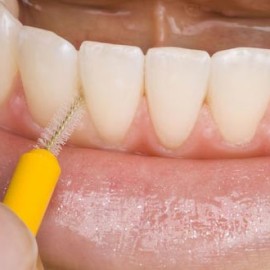

Encías sanas, cavidad bucal contenta

Unas encías sanas te permiten evitar esa apariencia inflamada y rojiza en la boca que podría avergonzarte al sonreír, además del dolor que ocasiona esta condición y el sangrado que produce al cepillarnos. Debes saber que una de las principales causas de la pérdida de dientes es la enfermedad en las encías o gingivitis. Pero Read More